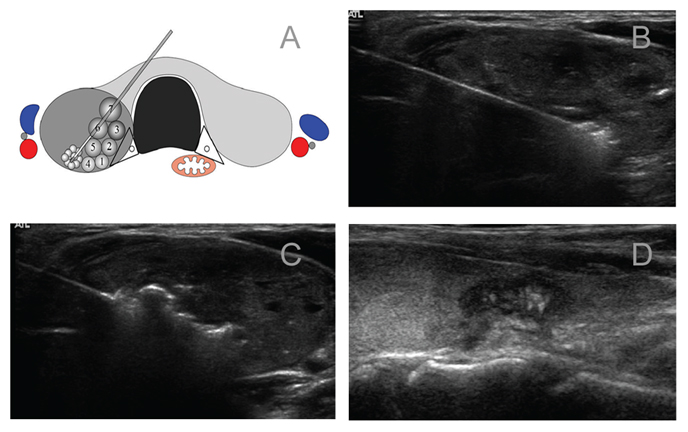

1.影像检查:超声或超声造影等,以详细了解甲状腺结节的位置、形态、大小、结节内部及周边血供情况及结节与周边结构的关系,确定最佳进针部位和途径。

五、热消融治疗术如何进行

1.患者取仰卧位,暴露颈部,由医师进行消毒,并铺无菌手术单

2.局部麻醉,穿刺进入颈部动/静脉及甲状腺外缘间隙,或者经峡部进入器官与甲状腺包膜间隙中注射生理盐水,形成水隔离带

3.将消融针在超声引导下逐渐穿入目标位置(一般多从结节的远处开始消融)

4.开通电源,逐渐后退消融针,完成一次消融后再更换消融路径,逐渐完成整个结节的消融

5.退针,消毒包扎,用冰袋冷敷,送回病房